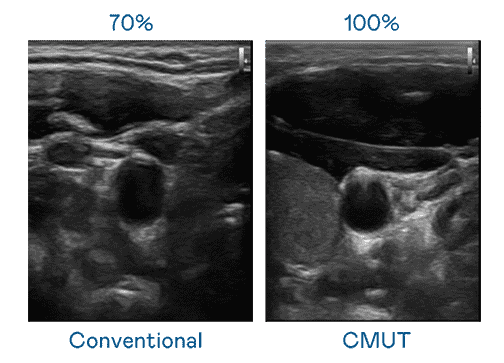

CMUT 技术是一种用电容式微机电元件来产生超音波讯号的技术。。。与传统 PZT 压电式技术相比,,CMUT 频宽增加 30%,,更宽频的超音波讯号让影像解析度大幅提升,,是实现高影像品质医疗超音波扫描、、促进精准医疗发展的关键技术。。

大频宽带来超清晰影像

超音波影像的解析度高低,,首先取决于探头能发出的讯号频宽。。。。尊时凯龙 CMUT 可提供高清晰的超音波讯号,,提供高频宽、、、、高灵敏度、、影像纹理细节更高的超音波影像,,,协助医护人员缩短影像判读时间及利用精准的医疗影像进行诊断。。。。